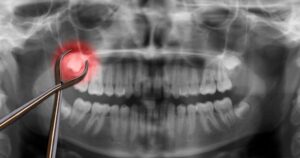

If you’ve recently had your wisdom teeth removed, you may be wondering what happens to the stitches placed during the procedure. A common question patients ask is: do wisdom teeth stitches dissolve on their own? In most cases, the answer is yes, but there are a few important details to understand about the healing process.